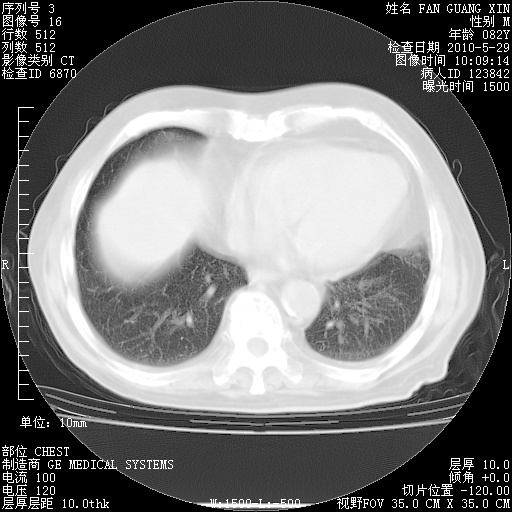

再治疗10天后的肺部CT